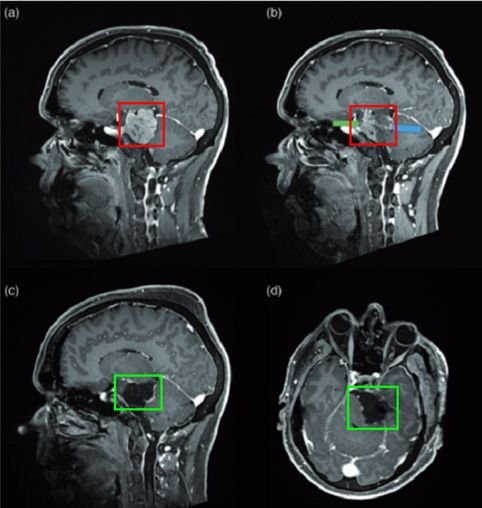

2005年,75歲的法國(guó)女士因右側(cè)海綿竇腦膜瘤進(jìn)行了一次開(kāi)顱手術(shù)。2016年,左側(cè)視力進(jìn)行性下降,檢查視力結(jié)果左側(cè)視力4.6(右側(cè)5.0),左側(cè)視神經(jīng)管內(nèi)側(cè)病變均勻增強(qiáng),還報(bào)告翼點(diǎn)空化是由顳肌萎縮引起的。診斷確定腦膜瘤位于視神經(jīng)管的中下側(cè)(圖1),導(dǎo)致了視力嚴(yán)重惡化。

手術(shù)方式:內(nèi)鏡輔助下右額下入路腫瘤全切術(shù)(圖2)

圖2:手術(shù)入路,右額下入路(入路方向大致如圖)

手術(shù)過(guò)程:一階段,通過(guò)鉆取蝶緣和內(nèi)側(cè)視神經(jīng)管進(jìn)行視神經(jīng)減壓術(shù),為后續(xù)手術(shù)做準(zhǔn)備。二階段經(jīng),經(jīng)額下入路(圖3)為對(duì)側(cè)交叉溝和視神經(jīng)提供絕佳手術(shù)通道,可以保障順利切除腫瘤(圖4)

·腫瘤完全切除(辛普森II)(圖5)

·視覺(jué)好轉(zhuǎn)

·嗅覺(jué)功能無(wú)損害/無(wú)腦脊液滲漏

術(shù)前及術(shù)后磁共振成像。術(shù)前preop(A)和術(shù)后Postop(C)顯示腫瘤完全切除,視神經(jīng)保留完好,無(wú)腦水腫、出血等。

圖5:術(shù)前及術(shù)后磁共振成像。術(shù)前preop(A)和術(shù)后Postop(C)顯示腫瘤完全切除,視神經(jīng)保留完好,無(wú)腦水腫、出血等。